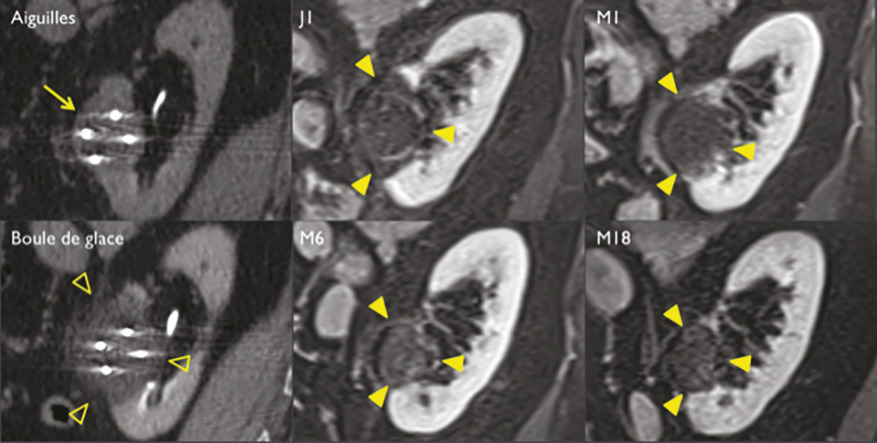

Pour chaque patient, un bilan d’hémostase est systématiquement réalisé avant la procédure. Pour les patients prenant des anticoagulants oraux, un relais par héparine de bas poids moléculaire est réalisé. Pour les antiagrégants plaquettaires, seul le clopidogrel doit être interrompu 5 jours avant. Le patient reçoit une prémédication par 1 g de paracétamol intraveineux 30 minutes avant la procédure. Il reste hospitalisé une nuit, mais une prise en charge ambulatoire est possible.La cryothérapie est réalisée sous anesthésie locale à l’aide d’un mélange de lidocaïne et de ropivacaïne. Contrairement à la radiofréquence ou aux micro-ondes où une seule électrode est insérée, la cryothérapie nécessite de mettre en place plusieurs aiguilles (cryoprobes) espacées au maximum de 15 mm afin de couvrir la totalité de la tumeur (fig. 1 ). Plus la tumeur est grosse, plus le nombre d’aiguilles à introduire est important. Il existe des abaques permettant de déterminer le nombre d’aiguilles optimal en fonction de la taille de la tumeur. Néanmoins, l’indication principale étant des tumeurs de stade T1a (< 4 cm de diamètre), le nombre moyen d’aiguilles est de 3, avec des extrêmes entre 2 et 5. Une injection de CO2 (carbodissection) ou de sérum physiologique (hydrodissection) est parfois nécessaire entre le rein et les organes adjacents afin de les éloigner de la zone d’ablation et les protéger.Les aiguilles sont mises en place sous tomodensitométrie et on vérifie leur bon positionnement. La dose délivrée lors d’une cryoablation rénale est inférieure aux niveaux de référence de dose recommandés pour une tomodensitométrie abdominale. Le traitement consiste en deux phases de cryoablation de 10 minutes entrecoupées d’une phase de réchauffement passif de 10 minutes également. L’effet cryogénique est obtenu par expansion d’un gaz (l’argon) dans une chambre de décompression de 2 à 4 cm de long située à l’extrémité de l’aiguille. Les températures minimales obtenues au contact de l’aiguille sont proches de -100 °C, en sachant qu’en moyenne la température de la tumeur se situe à -40 °C. La tomodensitométrie permet une excellente visualisation de la boule de glace, ce qui permet de monitorer l’ablation tout au long de la procédure. La boule de glace ainsi créée doit englober en totalité la tumeur et la dépasser de 5 mm afin d’avoir des marges de sécurité (fig. 2 ).6 En effet, le bord de la boule de glace est à l’isotherme 0 °C, qui n’est pas létal pour les tissus.Après traitement, le suivi des patients s’effectue par tomodensitométrie ou par imagerie par résonance magnétique (IRM), typiquement à 1 mois, 3 mois, 6 mois et 1 an, puis tous les ans. La zone d’ablation se rétracte progressivement et se fibrose, sans tumeur résiduelle visible (fig. 3 ). Pour les tumeurs de moins de 2 cm, le zone d’ablation disparaît parfois en totalité, laissant juste une encoche à la surface du rein (fig. 4 ). Les effets secondaires sont rares, la cryoablation étant mieux tolérée que les techniques d’ablation fondées sur le chauffage des lésions, en particulier pour les lésions proches de la voie excrétrice.7